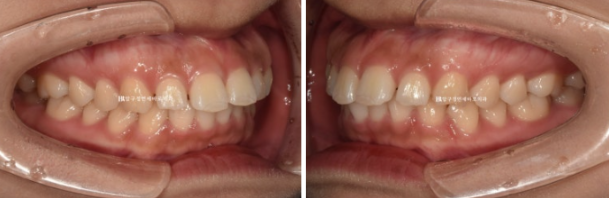

24.02

어금니 교합은 좋습니다.

이렇게 어금니 교합이 좌우 I급이면 인비절라인 라이트의 완벽한 적응증입니다.

앞니 사이 벌어진 공간을 모으고 약간의 치간삭제를 동반하여 돌출감도 어느정도 해결하는 것을 목표로 삼았습니다.

인비절라인 라이트 권유드렸고 2월에 장치 오더 그리고 3월부터 1단계 장치를 끼기 시작했습니다.